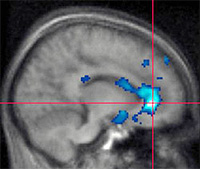

Imagen de actividad cerebral, obtenida mediante fMRI (resonancia magnética funcional), durante una sesión de utilización de videojuegos violentos, en la que se aprecia una activación en la corteza prefrontal, zona característica de la actividad cognitiva agresiva (Universidad de Michigan)

Es lo que los adultos deben saber en relación con la inteligencia digital relacionada con los videojuegos y las videoconsolas, en cualquier lugar que estén y en cualquier rol que desempeñen: fabricantes, dibujantes, promotores y vendedores natos de videojuegos. La industria del videojuego al fin. Los padres, las madres y los tutores. Las maestras y los maestros. Las profesoras y los profesores. Las amigas y los amigos. Todas y todos. Porque no hay recetas, ni prontuarios, ni guías de uso mágicas para controlar el uso de estas tecnologías, aunque sí actuaciones preventivas preparadas por profesionales (4). Porque hay videojuegos necesarios e innecesarios y porque la idoneidad de uso no la puede marcar solo una etiqueta aunque esté hecha con muy buena voluntad. Un videojuego debe ser una ayuda para el desarrollo de cada cerebro y no vale cualquier videojuego para cualquier cerebro adolescente, porque detrás de este cerebro individual (sabemos ya que no hay dos cerebros iguales) hay millones de años que justifican que tomemos muy en serio el cerebro de cada niña, de cada niño, de cada joven, porque sabemos científicamente que se está formando siempre en una dirección única: la inteligencia está al final de esta aventura humana en la historia de la humanidad, porque ha tenido que vencer antes batallas durísimas contra la violencia y las guerras, contra el hambre y la soledad para llegar hasta aquí. Ahí están las estructuras cerebrales para demostrárnoslo fehacientemente, a pesar de que la industria del videojuego sea cada vez más floreciente. Que me perdonen los dibujantes que participan en esta historia, la industria del videojuego y de las videoconsolas en general, porque ni Bambi (ayer) ni Mortal Kombat deben suplir las necesidades de unos cerebros que necesitan formarse en una realidad que el sistema límbico ha logrado demostrar cuando buscan cualquier arca perdida en la vida: más vale que dos personas caminen juntas porque una sola corre siempre el riesgo de perderse. Porque de lo contrario, sabemos científicamente que, por ejemplo, los videojuegos violentos activan una zona del cerebro, la corteza prefrontal, característica en la actividad cognitiva agresiva: “Los videojuegos violentos han sido acusados muy a menudo de potenciar reacciones, actos y comportamientos violentos. Hemos probado que existe esta relación a nivel neurobiológico” (5). No hay vuelta de hoja.